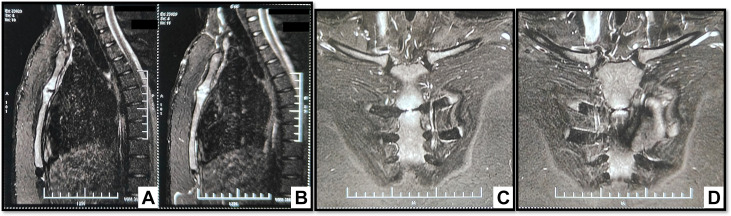

➤胸部磁共振成像(MRI):胸骨柄关节骨髓信号异常——T1加权像呈等低信号,T2加权像/短反转时间反转恢复序列(T2/STIR)呈高信号,弥散加权成像/表观弥散系数(DWI/ADC)序列显示弥散受限,提示骨髓水肿(图2);未观察到胸骨前或胸骨后软组织肿块及脓肿。

图2-胸部矢状位(A、B)及冠状位(C、D)T2-STIR加权MRI:胸骨柄关节两侧可见高信号区,无相关软组织肿块/积液,提示骨髓水肿。(STIR-T2W=短反转时间反转恢复T2加权)